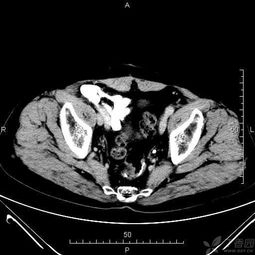

一,檢查前病人禁食即可.二.腹部檢查之前不能做其它造影檢查,尤其不能用鋇劑行消化道造影,以免腸內(nèi)殘留的造影劑形成偽影,影響ct圖像質(zhì)量,從而導(dǎo)致誤診.

各部位增強(qiáng)掃描及腹部平掃者,檢查前至少禁食四小時.

腹部檢查者,檢查前三日內(nèi)不食重金屬類物及不作鋇餐檢查.

需增強(qiáng)掃描者,檢查前需禁食一餐且三日內(nèi)不食重金屬類物及不作鋇餐檢查.